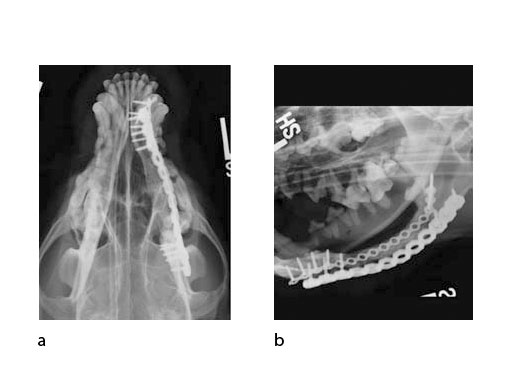

Follow-up x-rays at 7 months postoperatively (ventrodorsal view and lateral oblique view) (Fig 6) show healing of the defect (and resorption of the CRM), which was documented with a Jamshidi biopsy of the center of the original gap (Fig 7). The biopsy was performed at the same time as partial plate removal (Mini Plate) due to the intraoral plate exposure.